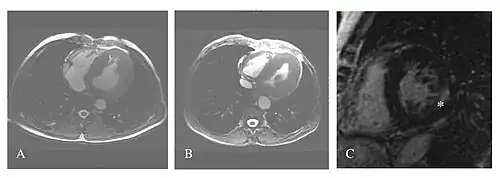

A Linksventrikuläre Hypertrophie (LVH) bei einem 51-jährigen dialysepflichtigen Patienten mit zerebrovaskulärer Beteiligung.

B 56-jähriger Patient mit hypertropher Kardiomyopathie und Herzrhythmusstörung, Leukoaraiose sowie Transplantatniere.

C Late-Enhancement-Messung nach der Gabe eines gadoliniumhaltigen Kontrastmittels bei einer 63-jährigen dialysepflichtigen Patientin.

Etwa 40 bis 60 % der Morbus-Fabry-Patienten zeigen kardiale Symptome wie linksventrikuläre Hypertrophie (LVH, Verdickung der Herzwände der linken Herzkammer), Herzrhythmusstörung (Arrhythmie), Angina Pectoris (anfallsartiger Schmerz in der Brust) und Dyspnoe (erschwerte Atemtätigkeit).[78][80][81][82][83] Die Herzrhythmusstörung und die beeinträchtigte Herzfrequenzvariabilität werden vom Sinusknoten, dem Erregungsleitungssystem, und einer Störung des Gleichgewichts zwischen sympathischem und parasympathischem Tonus hervorgerufen. Diastolische Dysfunktionen und linksventrikuläre Hypertrophien sind wichtige Symptome des Morbus Fabry. Für Männer sind diese Symptome grundsätzlich schwerwiegender als für Frauen. Myokardischämien (Durchblutungsstörungen des Herzmuskels) sind die Folge einer schlechten Koronardurchblutung.[84]

Im Alter entwickeln sich progredient Myokardfibrosen, die sowohl reversibel interstitiell als auch irreversibel narbig (replacement fibrosis) sind.[85][86] Die irreversiblen narbigen Fibrosen bilden sich in fast allen Fällen zuerst in der hinteren seitlichen Herzwand und im Midmyokard. Bei Patienten im Endstadium reduziert eine transmurale (die gesamte Dicke der Wandschicht des Herzens betreffende) narbige Fibrose allmählich die Herzfunktion bis zur kongestiven Herzinsuffizienz.[87][88][89][90] Maligne Arrhythmien sind für die meisten Fälle von Herztod bei Morbus-Fabry-Patienten verantwortlich.[7][83][90]

Die linksventrikulären strukturellen Veränderungen des Herzens finden sich bei Morbus-Fabry-Patienten häufig. Mittels Echokardiografie (Ultraschalluntersuchung des Herzens) oder kardialer Magnetresonanztomographie (MRT) können die meist konzentrischen Hypertrophien[80][81] sichtbar gemacht werden. Da mit zunehmendem Alter durch die Ersatzfibrose die linksventrikuläre Hinterwand des Herzens immer dünner wird, ist die Messung der Septumdicke – das ist die Stärke der Scheidewand zwischen linker und rechter Herzhälfte – besonders wichtig. Unabhängig von den strukturellen Veränderungen scheint die Systole, die Phase, in der das Blut aus der linken und rechten Herzkammer herausgepresst wird, bei der Messung mit konventionellen Methoden weitgehend erhalten zu bleiben.[80][81][82][91] Die durch Morbus Fabry verursachte Kardiomyopathie ist durch eine reduzierte Kontraktion und Relaxation des Herzmuskels gekennzeichnet. Gewebedoppler (sowohl tissue velocity imaging als auch strain rate imaging) kann die Herzmuskelfunktion quantifizieren.[7][92] Mit dieser Methode kann die Kardiomyopathie noch vor der Entwicklung einer linksventrikulären Hypertrophie diagnostiziert werden.[91][93]